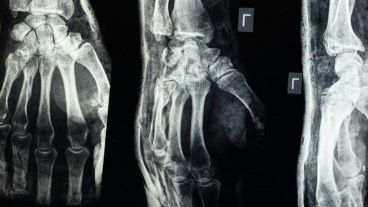

En un caso de prueba, un paciente con una fractura de muñeca recibió una inyección a través de una incisión de apenas 3 cm y se curó en solo tres minutos, según informó el medio chino Cho Sun Daily. Después de un control de seguimiento de tres meses, la fractura del paciente se había curado completamente sin complicaciones.